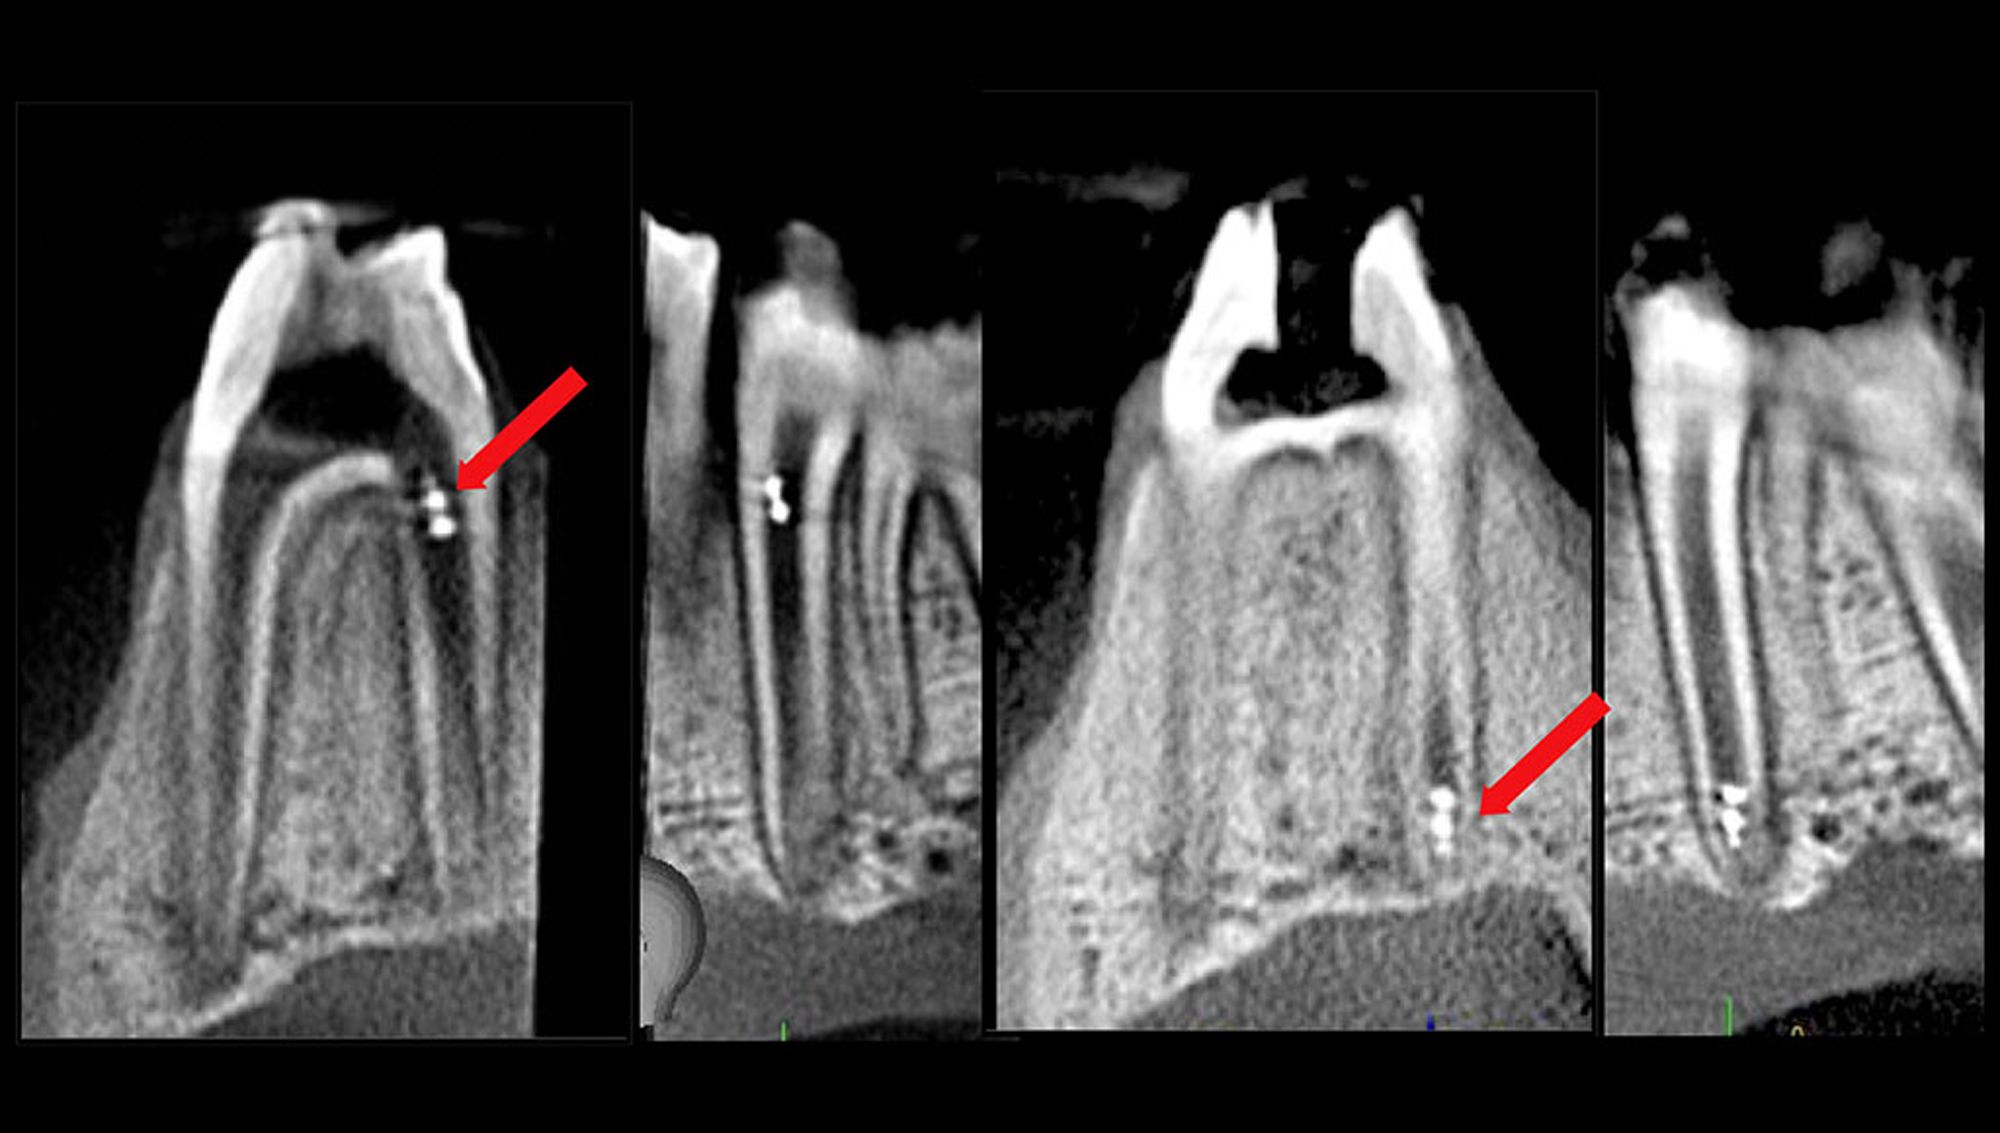

This study was done using 3D printed tooth replicas and mixed species biofilm containing endodontic bacteria. Microrobots were tracked in real time using an intraoral scanner, an X-ray, and cone beam computed tomography. This allowed for a visible maneuverability, according to Chair of Penn Dental Medicine’s Department of Endodontics, Dr Bekir Karabucak.

“Importantly, we demonstrated in an ex vivo model that the robots could be controlled by the magnetic field without interrupted by the soft and hard tissue surrounding the tissue,” Dr Karabucak said in the press release. “In addition, they showed tremendous maneuverability from the top to the bottom of the canal.”